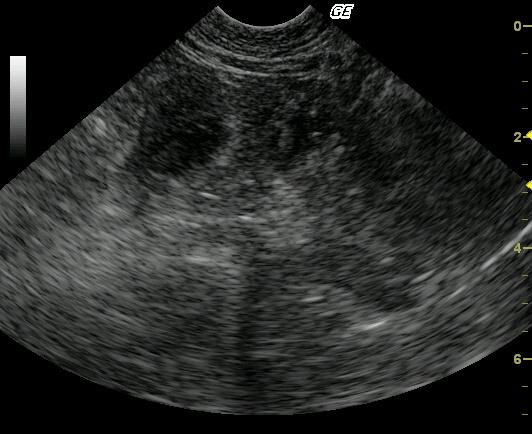

This image shows marked, circumferential, slightly asymmetrical, focal bowel wall thickening. The affected bowel wall is hypoechoic, heteroechoic, lacks layering, and possesses a slightly undulating serosal margin. The peri-intestinal mesentery and omentum are echogenic, most notably within the far field.

Differential diagnoses included an intestinal wall mass with suspicion of multifocal ulceration and peri-intestinal inflammation. Partial omental and/or mesenteric adhesion cannot be definitively ruled out. These findings would be most consistent with neoplasia. Inflammatory or granulomatous diseases were considered less likely.